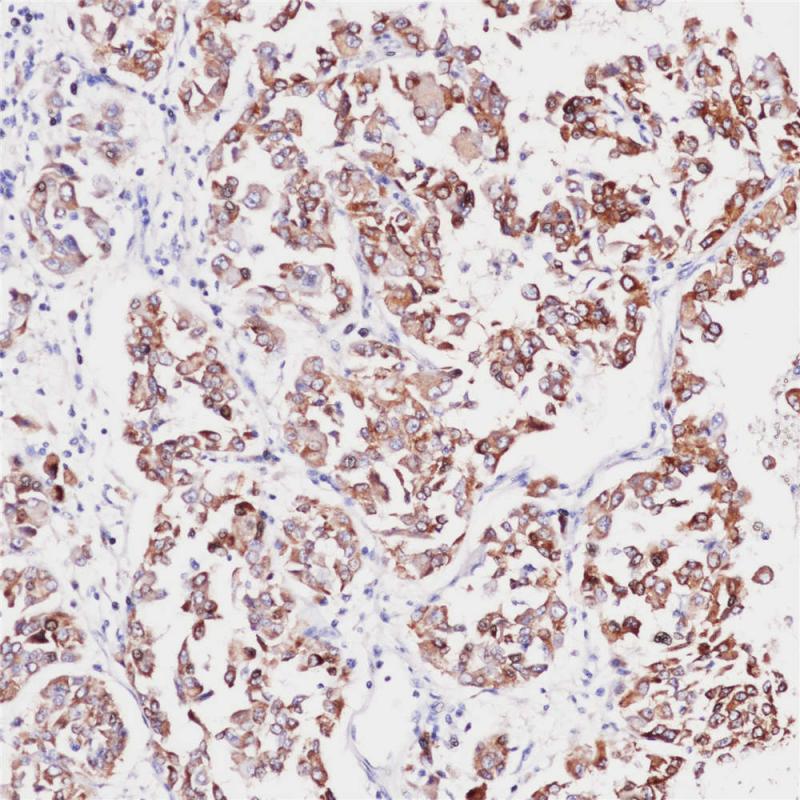

Mammaglobin 重组兔单克隆抗体

Mammaglobin 也称乳腺珠蛋白,是一种特异地表达于乳腺上皮细胞、原发性乳腺癌组织的分泌性球蛋白。该抗体具有极强的乳腺组织特异性,在正常淋巴结和非乳腺癌转移淋巴结中一般均不表达,能较好地诊断乳腺癌淋巴结微转移。

阳性对照

乳腺癌

亚细胞定位

细胞质